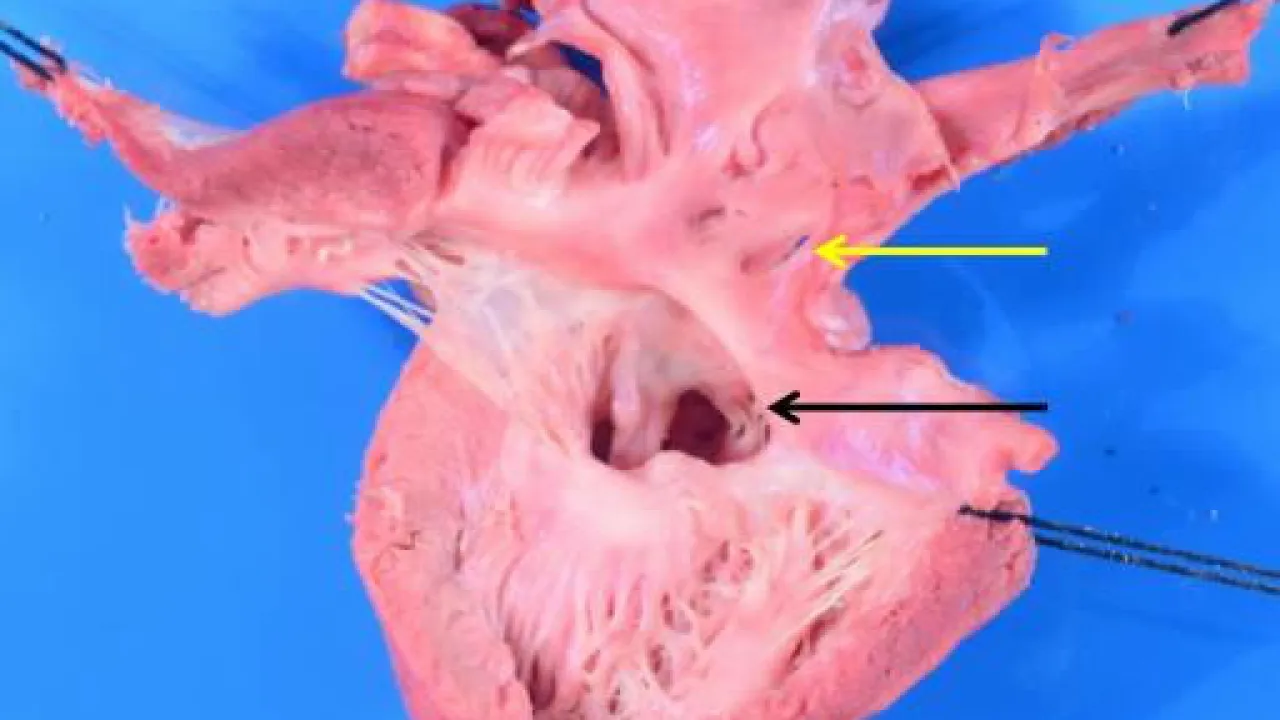

Heart, Atrioventricular septal defect